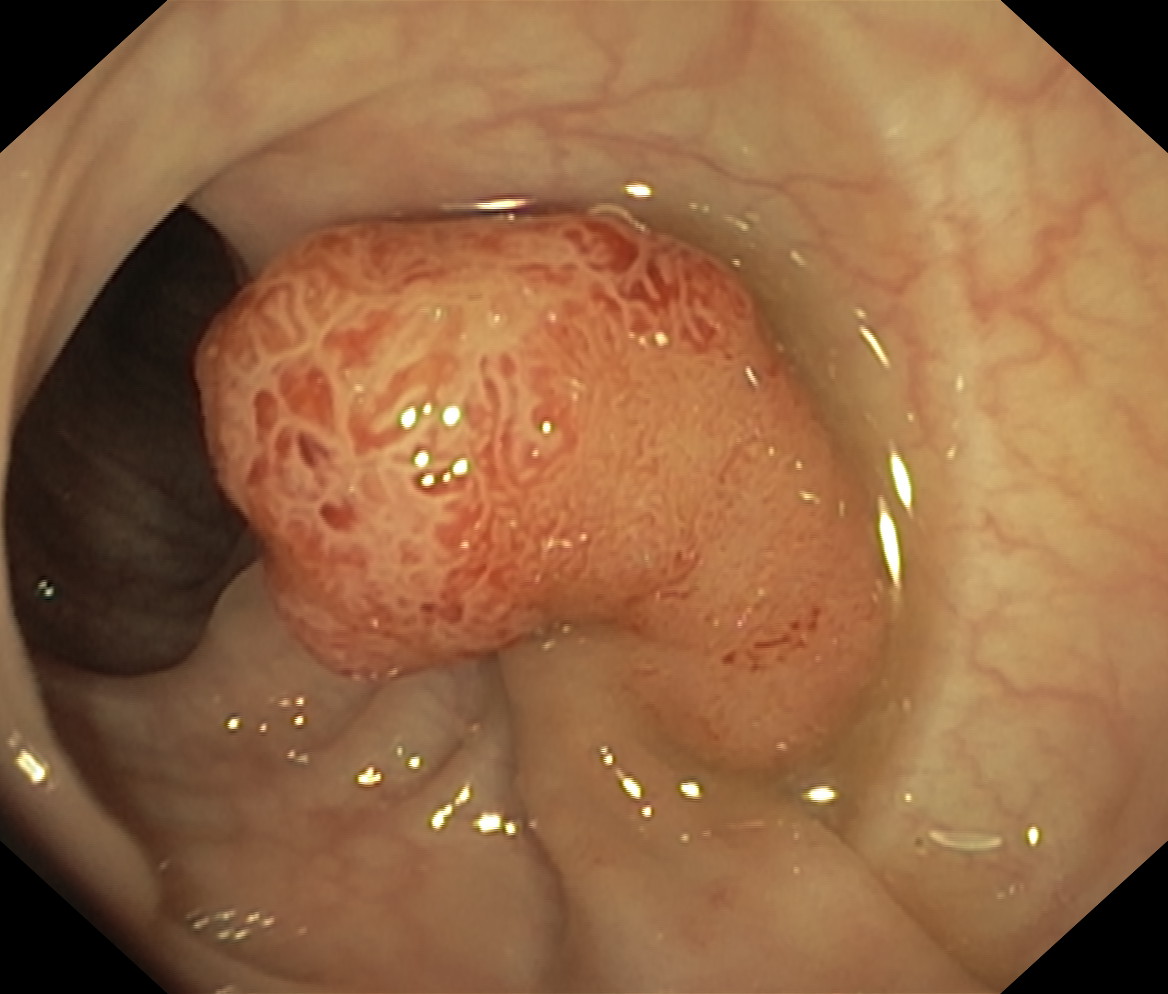

Polipy